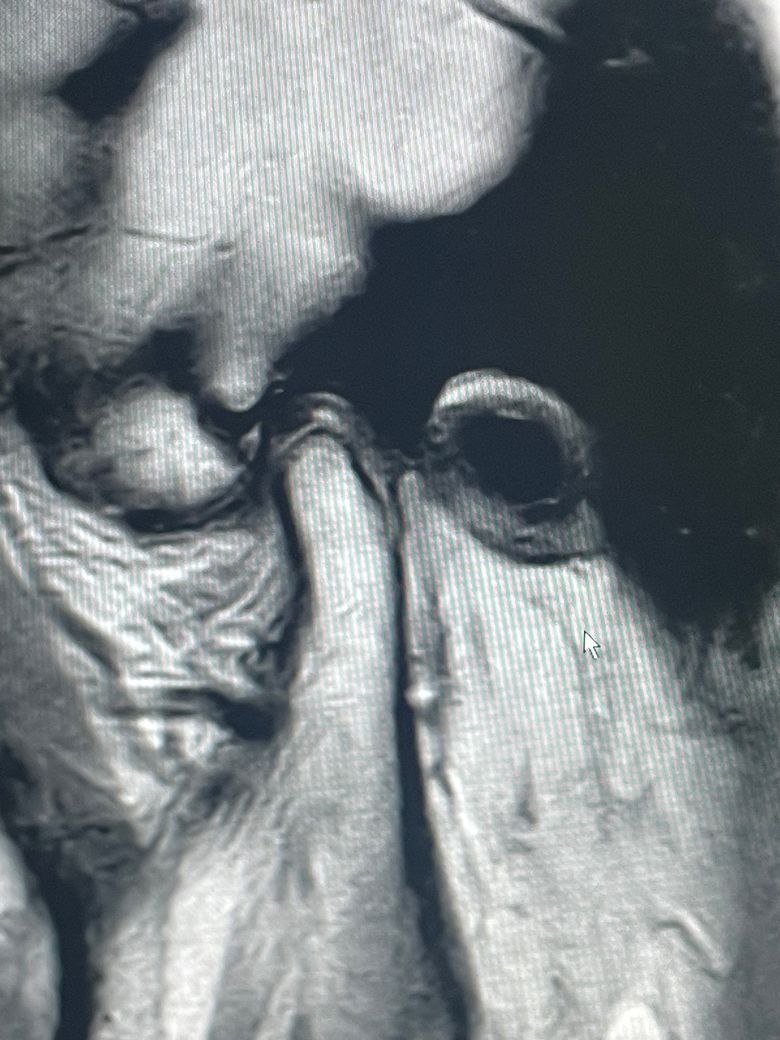

턱관절 mri 봐주세요 구강내과 치과

같은 mri를 갖고가도 판독이 다 달라서 올립니다

일반인이 봐도 하악과두 위에 잘 있는 거 같긴 한데 그럼 제 증상은 뭘까요ㅠㅠ

순서대로 왼쪽 턱 사진 오른쪽 턱 사진이에요

턱관절 질환이 있다면 턱의 위치가 일시적으로 변하는 듯한 느낌이 들 수 있습니다. 턱관절 질환은 결과적으로 턱에 가해지는 힘이 강해서 생기는 증상이기 때문에 턱에 가해지는 힘을 줄여주는 것이 좋습니다. 턱에 가해지는 힘은 치아가 닿음으로써 가해지기 때문에 치아를 살짝 떨어뜨리고 있는 습관을 들인다면 턱관절 질환을 줄일 수 있습니다. MR아이 상에서는 정확한 판독이 어려워보이나 움직임을 할 때 걸리는 느낌이 있다면 디스크가 비정상적으로 위치하고 있을 가능성이 높습니다.

증상을 봐서는 턱관절 주변의 근육 문제일 것 같습니다. 찐득한 음식을 반복 저작하는게 트리거가 됐을 것 같네요.

턱관절 뼈에는 특이사항은 없어보입니다.